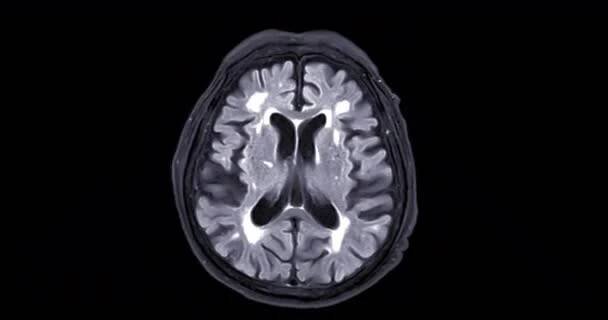

Magnetická rezonance (též MR, MRI, z anglického „magnetic resonance imaging“) je zobrazovací technika používaná především ve zdravotnictví k zobrazení vnitřních orgánů lidského těla.

Magnetické rezonanční zobrazování (také označovaná jako MRI - zkratka z Magnetic Resonance Imaging) je test, který využívá silné magnety, rádiové vlny a počítač pro vytváření detailních snímků uvnitř těla.

MRI mozku nebo magnetická rezonance mozku pro diagnostiku mozkových nádorů a cévní mozkové příhody. — Stock záběr